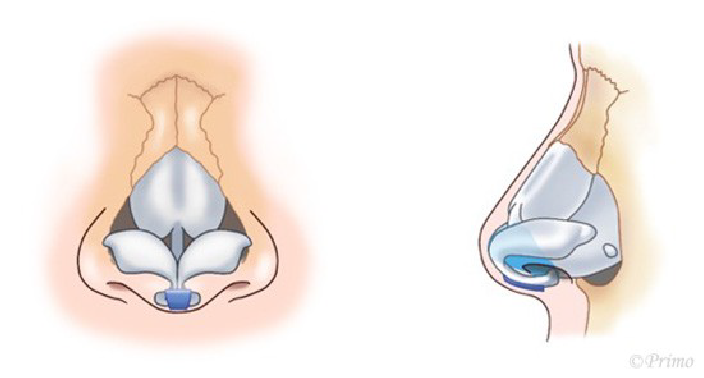

求める変化の大きさ、もともとの鼻の状態に応じ、採取部位を耳介軟骨、肋軟骨、あるいは鼻中隔軟骨から選択し、必要量のみ採取いたします。(上の図は耳介軟骨を採取して鼻中隔延長をするイメージ)

耳介軟骨からとる場合は、耳の後ろのしわに沿って約2cm程の傷から採取します。傷はほとんどわからなくなり、耳の変形も、機能障害もきたしません。

肋軟骨からとる場合は、バストのアンダーの位置に約3cm程の傷から採取します。傷は最小限になるよう形成外科縫合を行います。移植材料となる軟骨が大きくとれるので、大きな変化を求める場合や、術後の修正例の場合に適しております。採取部の変形などはありません。

鼻中隔軟骨から採取する場合は、軟骨が小さいため、それほど大きな変化を望まない場合などになります。別の所に採取部の傷を残さない良い方法です。(下の図は鼻中隔)

アプローチは経鼻柱切開(オープンアプローチ)から、術野を広く展開し、確実に操作を行います。鼻中隔軟骨に移植軟骨を組み合わせ延長し鼻の向き、高さを変えていきます。ご希望に応じ鼻の脂肪を部分的に除去し細っそりとさせたり、インプラントによる隆鼻術を併用し、より印象的な鼻に変化させます。鼻柱の傷あとはあまり目立ちません。

青い部分が移植した軟骨です。この軟骨の固定により、鼻の高さ、細さ、向きが大きく調節できます。